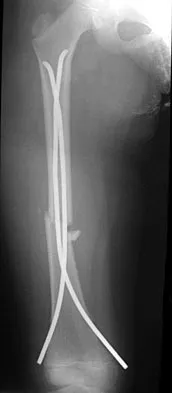

Question 16

Figure 22 shows the radiograph of a 7-year-old boy who underwent retrograde elastic nailing of a femoral shaft fracture. What is the most common problem following this procedure?